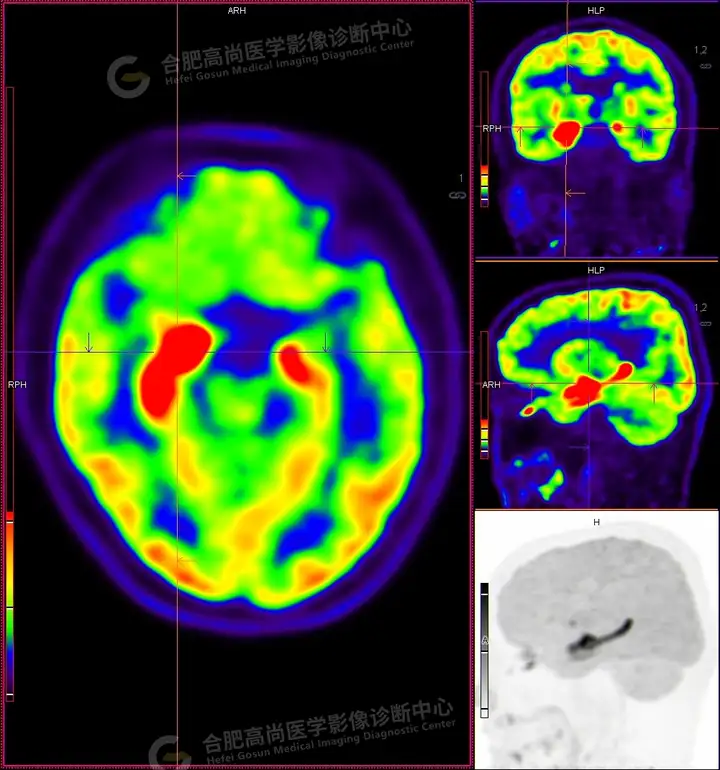

18F -FDG PET/CT检查图像:

18F -FDG PET/CT检查所见:

发作间期显像:PET显像双侧海马呈放射性摄取异常增高,以右侧明显,右侧海马SUVmax16.1、SUVavg4.4,左侧海马SUVmax7.3、SUVavg3.1(同层面额叶脑皮质SUVmax5.9、SUVavg2.3);CT示左侧海马体积较右侧似轻度缩小,左侧侧脑室颞角轻度增宽。PET显像右侧杏仁核及右侧基底节区局灶性放射性摄取异常增高,SUVmax14.1、SUVavg5.7(左侧SUVmax5.1、SUVavg3.6);CT示右侧杏仁核及右侧基底节区大小、形态正常,未见异常密度灶。

18F -FDG PET/CT检查结论:

发作间期显像:双侧海马、及右侧基底节区FDG代谢异常增高,考虑致癫灶可能大,请结合临床。